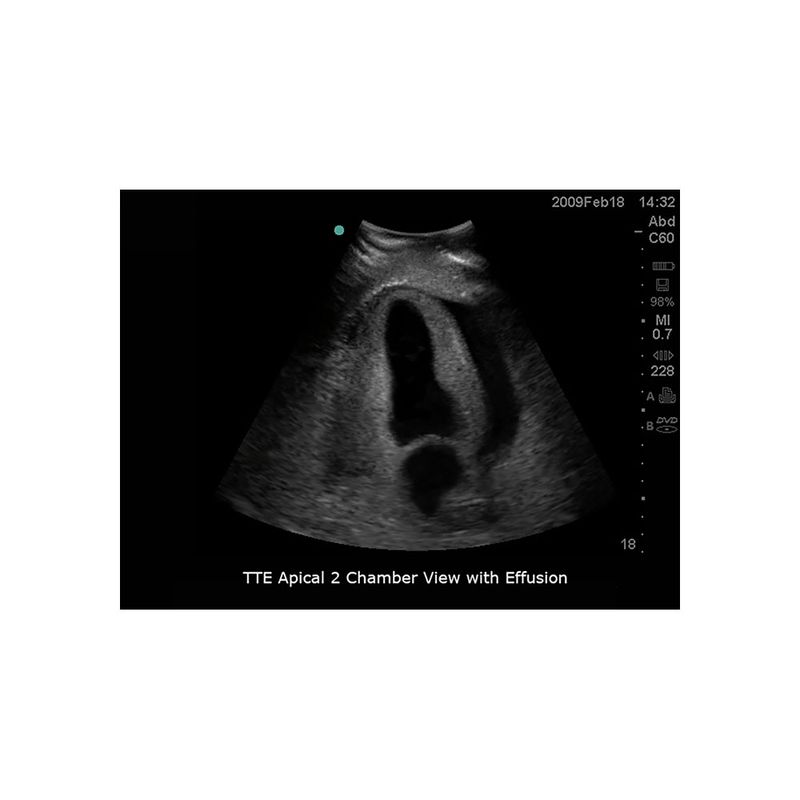

模型具有精准的内外部解剖结构,能与任何带经食道超声探头、心脏探头及腹部探头的超声影像检查设备联合使用,可进行经食道超声心动图(TEE)、经胸廓心超声心动图(TTE)、超声引导下心包穿刺术等完整操作流程训练。适合于心血管内科、急诊科、重症医学科、超声科等学科使用。